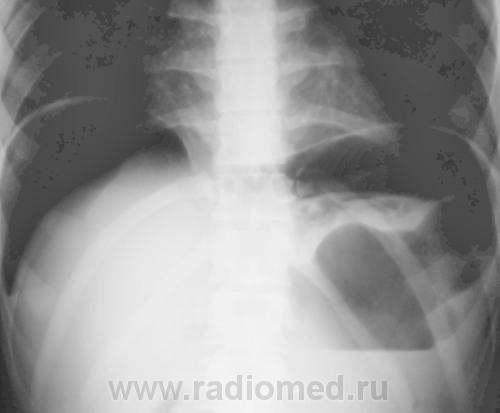

Да, на обзорге ОГК стенка свода желудка ровная, тонкая (париетография прям). А на РГ ОБП между газом слева и пузырем желудка какая-то тень, может кровь натекла?

А рана где? Может это внутристеночная гематома желудка (негомогенно смотрится). Однако же, коллеги, ну пофантазируйте: вот два снимка, на одном стенка свода линейная, на втором - нет. Что это (кроме занудного ответа "скиалогия":)

Газ в брюшной полости понятен.Не понято,что в желудке.

Нет,там сверху что-то свисает,могу ошибаться.

Интересен промежуток времени между снимками...

Между снимками промежуток в 2 минуты

Со слов оперировавшего хирурга, большое количество крови было в сальниковой сумке...